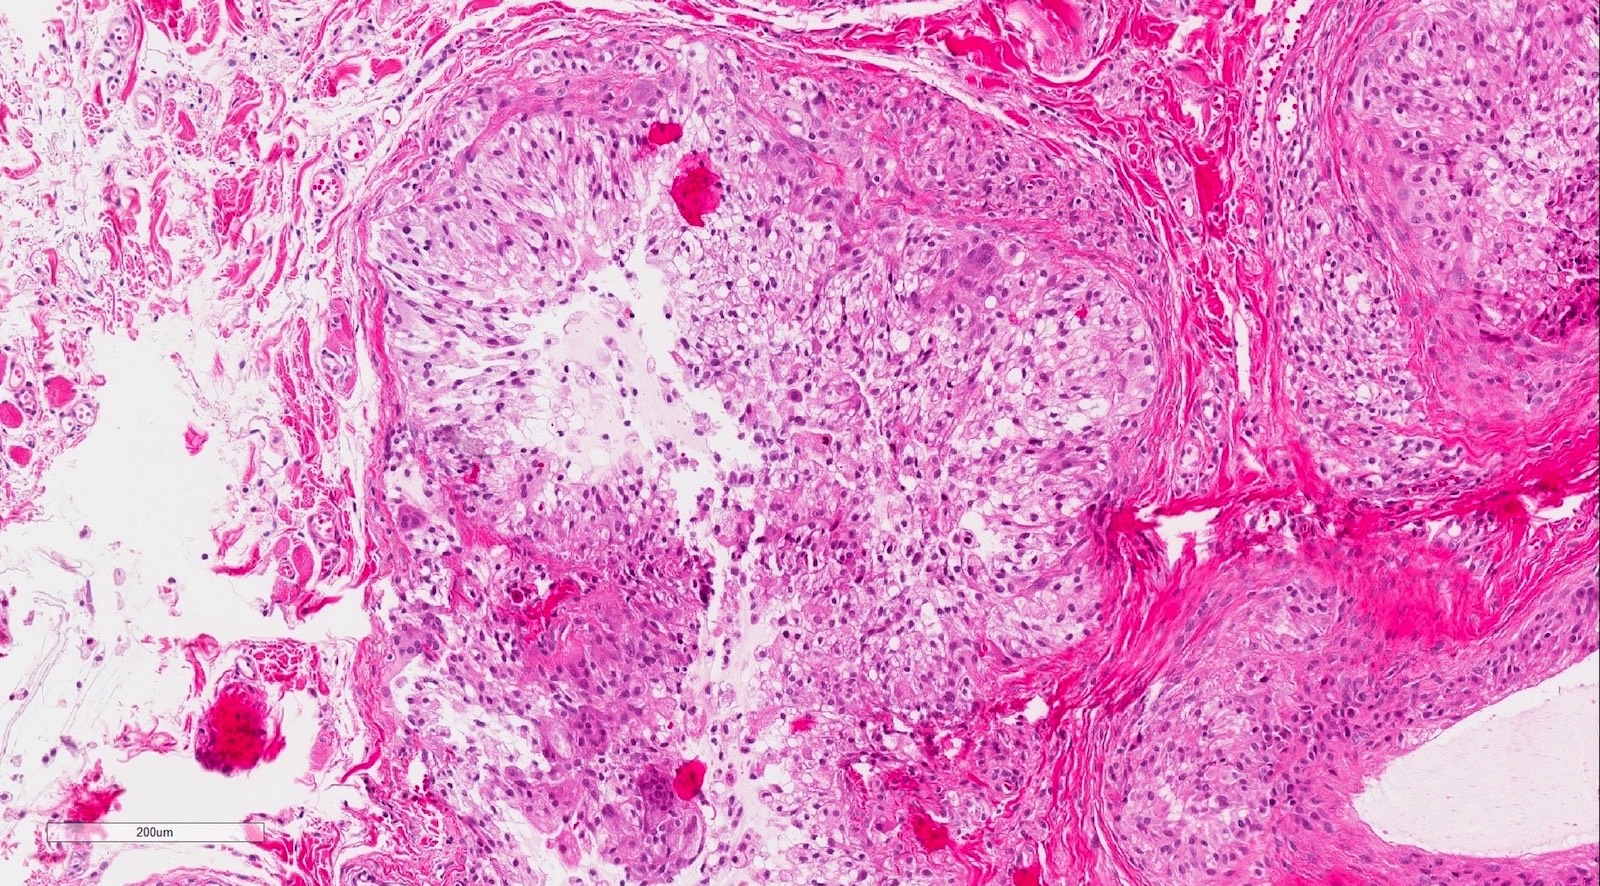

Microscopic (histologic) description

- If removed intact

- Pseudocyst cavity containing mucin, abundant epithelioid foamy histiocytes (muciphages), neutrophils and granulation tissue (Acta Histochem 2014;116:40)

- If removed ruptured

- Fragments of granulation tissue containing epithelioid foamy histiocytes (muciphages) and neutrophils, may see mucinous material (Acta Histochem 2014;116:40)

- Removed salivary gland parenchyma showing obstructive changes

- Acinar atrophy, ductal dilatation with periductal hyalinization, interstitial lymphoplasmacytic infiltrate and interstitial fibrosis at late stage (J Oral Maxillofac Surg 2008;66:2050)

- May see ruptured feeding salivary duct with squamous metaplasia (J Oral Maxillofac Surg 2008;66:2050)

- Long standing lesions organize into fibrosis resembling a fibroepithelial polyp (Acta Histochem 2014;116:40)

- No epithelial cyst lining, may see overlying surface oral mucosa with variable atrophy in superficial mucoceles (J Oral Maxillofac Surg 2011;69:1086)

Microscopic (histologic) images